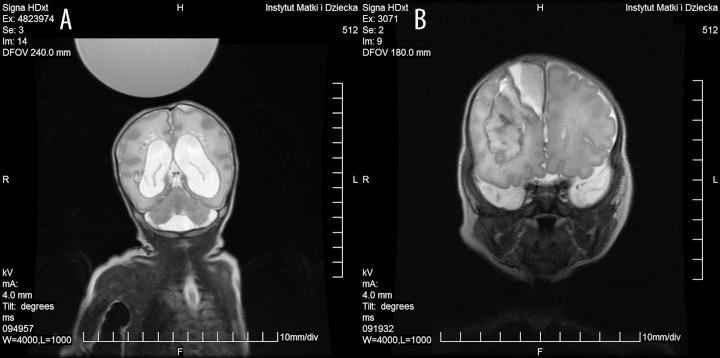

MATERIAL/METHODS: Examinations were performed in 27 newborns (12 girls, 15 boys). Most of the neonates were prematurely born: 19 (70.4%) were born at gestational age of 23-37 weeks, mean of 30 weeks. They were examined at the corrected age of 26 weeks-1 month, mean of 36 weeks. Body weight of the newborns on the day of the study was 600-4,300 g, mean of 2,654 g. The study was performed with a GE Signa HDxT 1.5 T system with the use of a Nomag IC 1.5 incubator by Lammers Medical Technology Co., equipped with three coils: an eight-channel, phased-array head coil and a twelve-channel phased-array coil for the whole body, consisting of an eight-channel coil integrated in the incubator and a separate four-channel surface coil.

Of the 27 children, 25 (92.6%) required a brain scan. Two children (7.4%) were referred to MRI for assessment of the spinal canal and the abdomen. We compared the results of transfontanelle ultrasound and MRI scans in 21 children. MRI provided significantly more diagnostic information in 18 cases (85.7%); in 3 cases (14.3%), no additional knowledge about the pathology was provided by the exam.